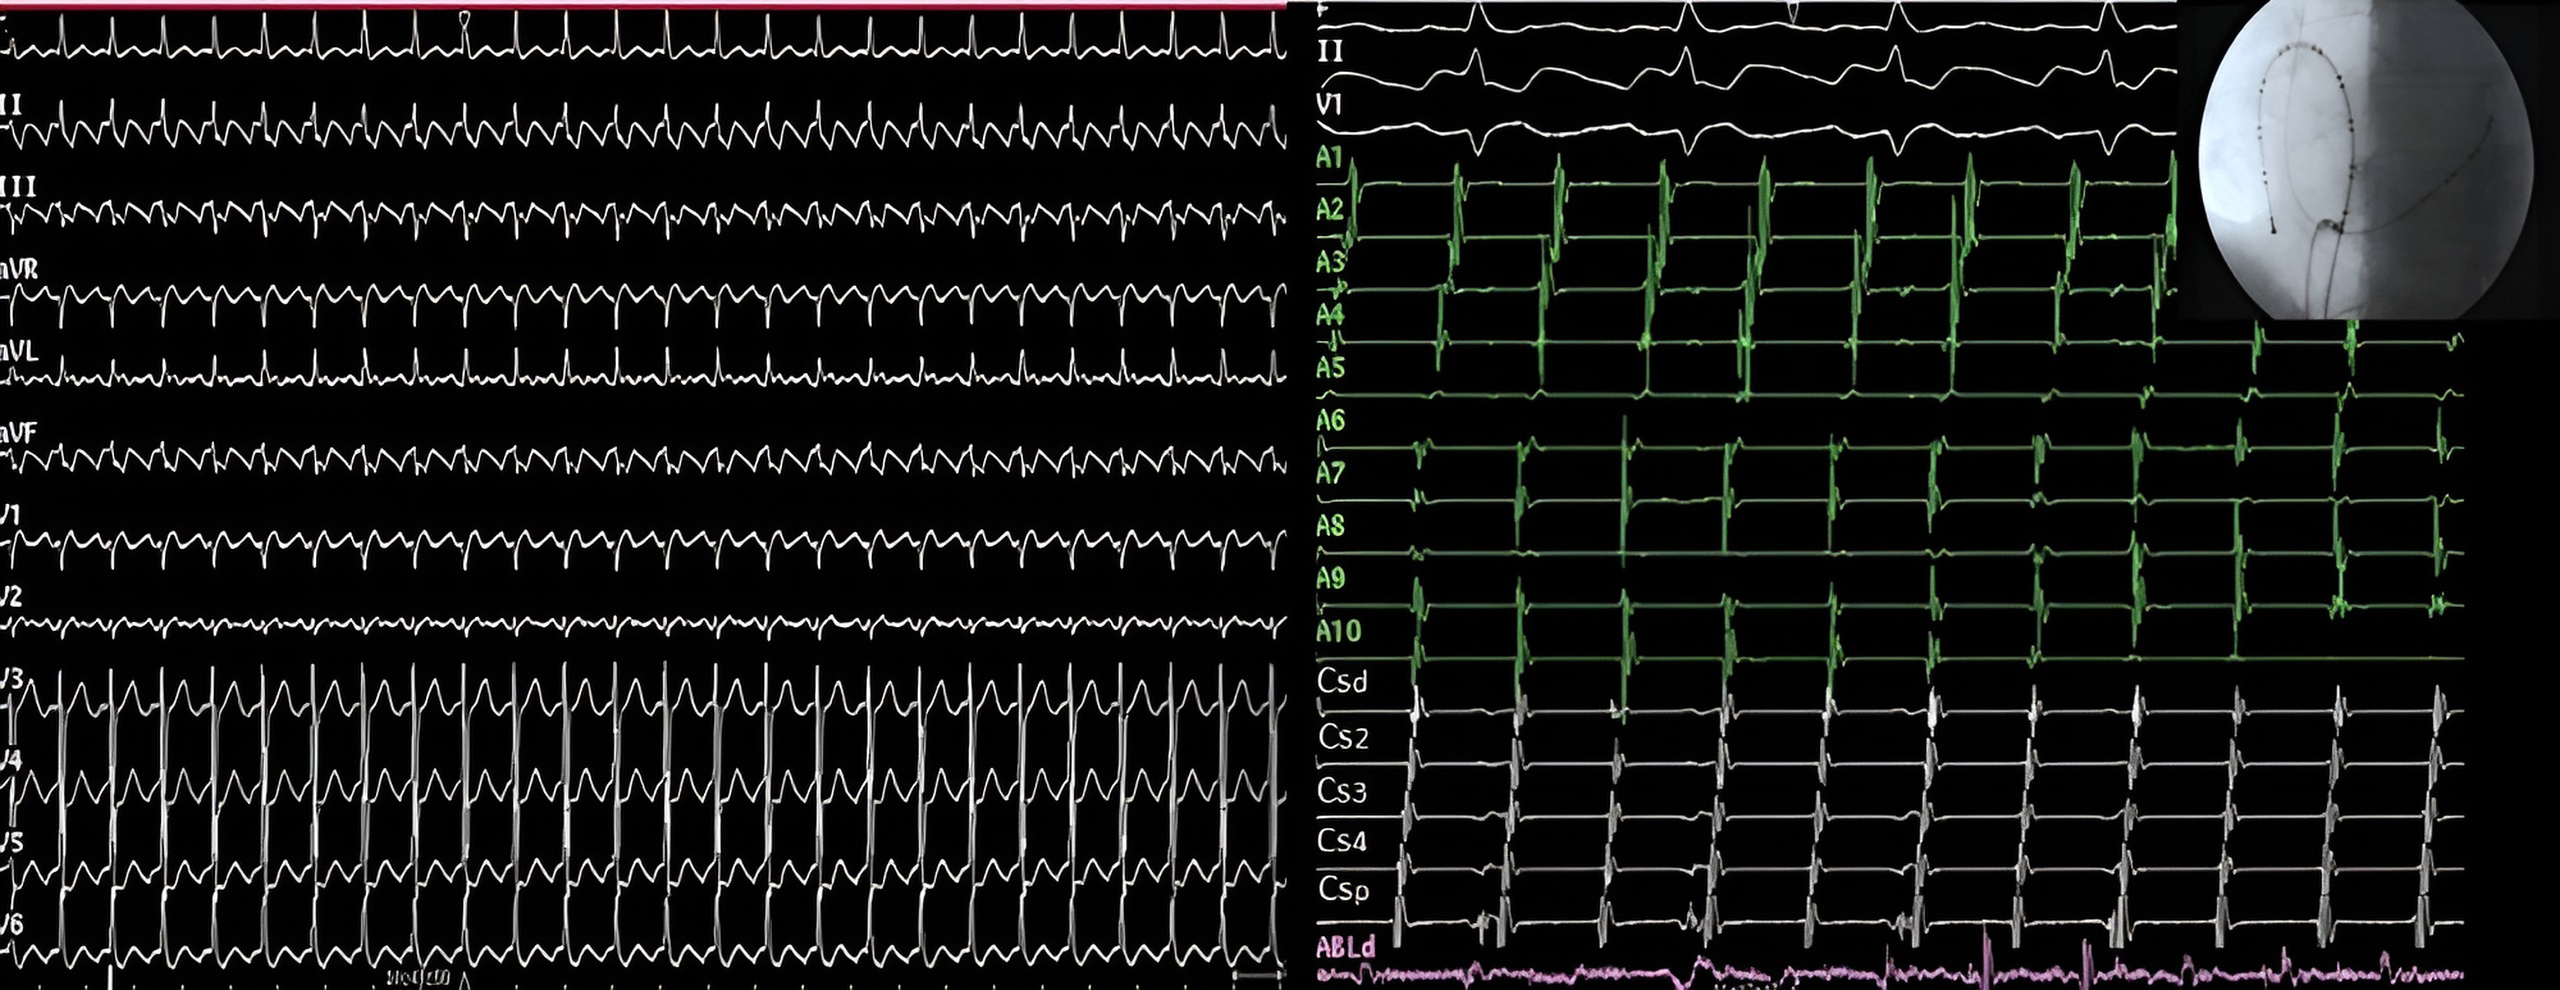

To confirm counterclockwise CTI block, pacing is performed from one of the dipoles of the duodecapolar catheter located on the lateral part of the CTI or directly with the ablation catheter (Fig. 13A). Conversely, to confirm clockwise CTI block, pacing is performed from the ostium of the coronary sinus (Fig. 13B). It is important to use relatively slow pacing frequencies to avoid rate-dependent CTI block [147].

Fig. 13.CTI block and non-inducibility evaluation. (A) Pacing from the low anterolateral right atrium (dipole A1) demonstrating ICT clockwise block. Activation of the RA is performed along the tricuspid annulus (A1-A10) until it reaches proximal coronary sinus (CSp). The administration of 3 extrastimuli does not induce any tachycardia. (B) Pacing from the coronary sinus os reaches the inferior septum (A10) and the activation wavefront is propagated toward A10-A1, demonstrating CTI counterclockwise block. CTI, cavotricuspid isthmus; RA, right atrium.